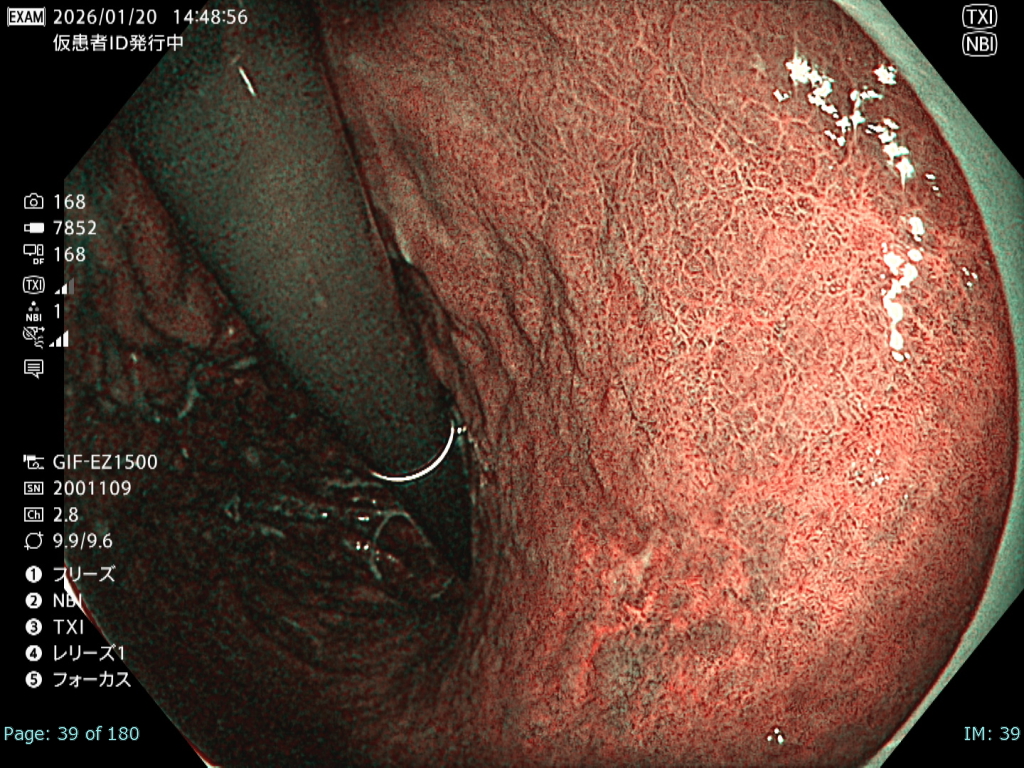

• NBI観察①(中遠景)

強調設定:B8

図3

観察中に出血が増加し、頻回の洗浄が必要となった。さらに胃管症例であったことから咳嗽が出現し、霧が生じるなど観察条件は不良であった。